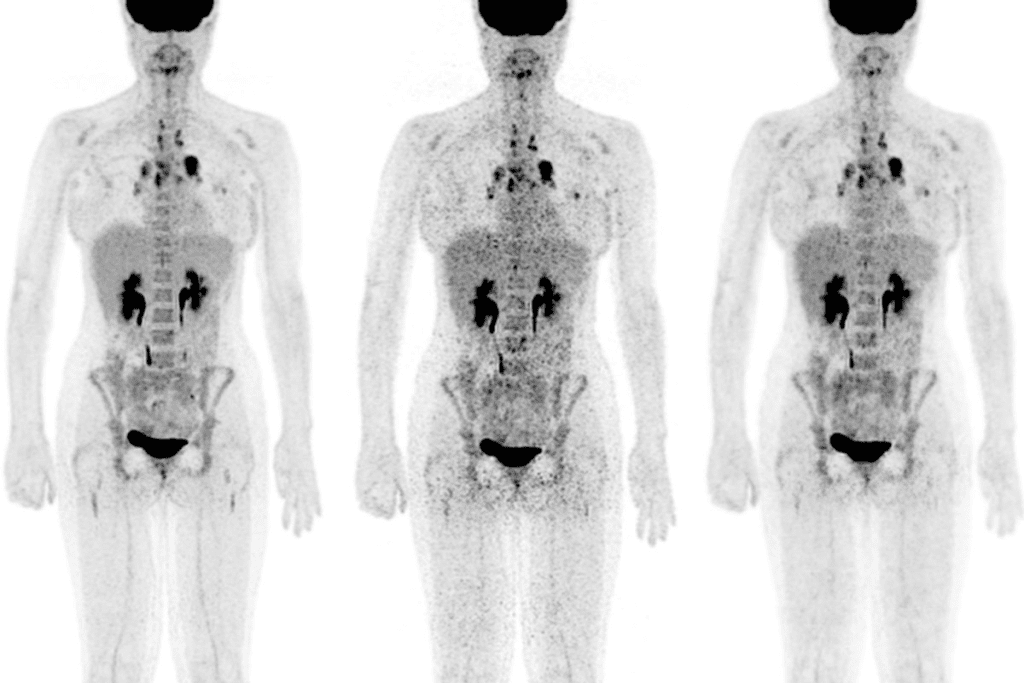

Cancer Detection and PET/CT Imaging

PET and CT scans together have changed how we find and treat cancer. We use PET/CT imaging to get a full picture of cancer. This method combines PET’s function info with CT’s body details, giving us a clearer view of the disease.

How Cancer Cells Appear on PET Scans

Cancer cells use more energy than normal cells, making them show up on PET scans. We use a special tracer, FDG, that cancer cells take up more of. This makes cancer cells show up as “hot spots” on the scan.

Staging and Evaluating Cancer Spread

Doctors need to know how far cancer has spread to make the right treatment plans. Accurate staging is key to finding the best care for cancer patients. PET/CT scans help us see how far the disease has spread, which is vital for treatment choices and patient results.

Determining the Extent of Disease

PET/CT scans are essential for finding out how far cancer has spread in the body. They combine PET scans’ functional info with CT scans’ anatomical details. This gives us a full picture of the disease, helping us figure out the cancer’s stage.

Identifying Metastasis Throughout the Body

PET/CT scans are great at spotting cancer spread in the body. They can find cancer in lymph nodes, bones, and other organs. Knowing this helps us understand how serious the disease is.